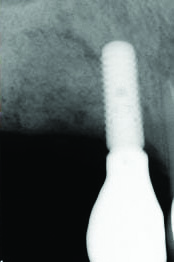

Fig 12. Case 2: Immediate postoperative radiograph. Note the tack securing the collagen membrane (upper left portion of the image).

Figure 12

The patient in case 2 received a crestal incision with full-thickness flap elevation, then tooth No. 5 was extracted (Figure 9). Implant debridement followed the same protocol used in case 1. FDBA was mixed with a small amount of doxycycline and placed around the implant (Figure 10). A resorbable collagen membrane (not pictured) was secured with a tack. Primary closure was achieved with expanded polytetrafluoroethylene (ePTFE) sutures (Figure 11). An immediate post-surgical radiograph showed bone fill and the tack (Figure 12).

The 12-month and 7-year follow-ups for case 2 showed similar improvements with normal soft-tissue healing and bone fill and normal pocket depths at 12 months (Figure 15 and Figure 16) and 7 years post-treatment (Figure 17 and Figure 18) (Table 1).